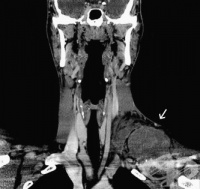

S25.1 Травма на безименната или подключичната артерия

Травма на безименната или подключичната артерия е рядко срещана травма, но трудна за управление. Тра...

S25.3 Травма на безименната или подключичната вена

Травма на безименната или подключичната вена може да се причини от проникваща травма или да бъде ятр...